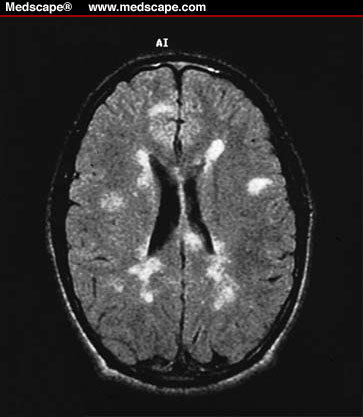

Multiple sclerosis- paraventricular white matter lesions

-multiple, bilateral, asymmetric hyperintense lesions representing clusters of demyelinated neurons